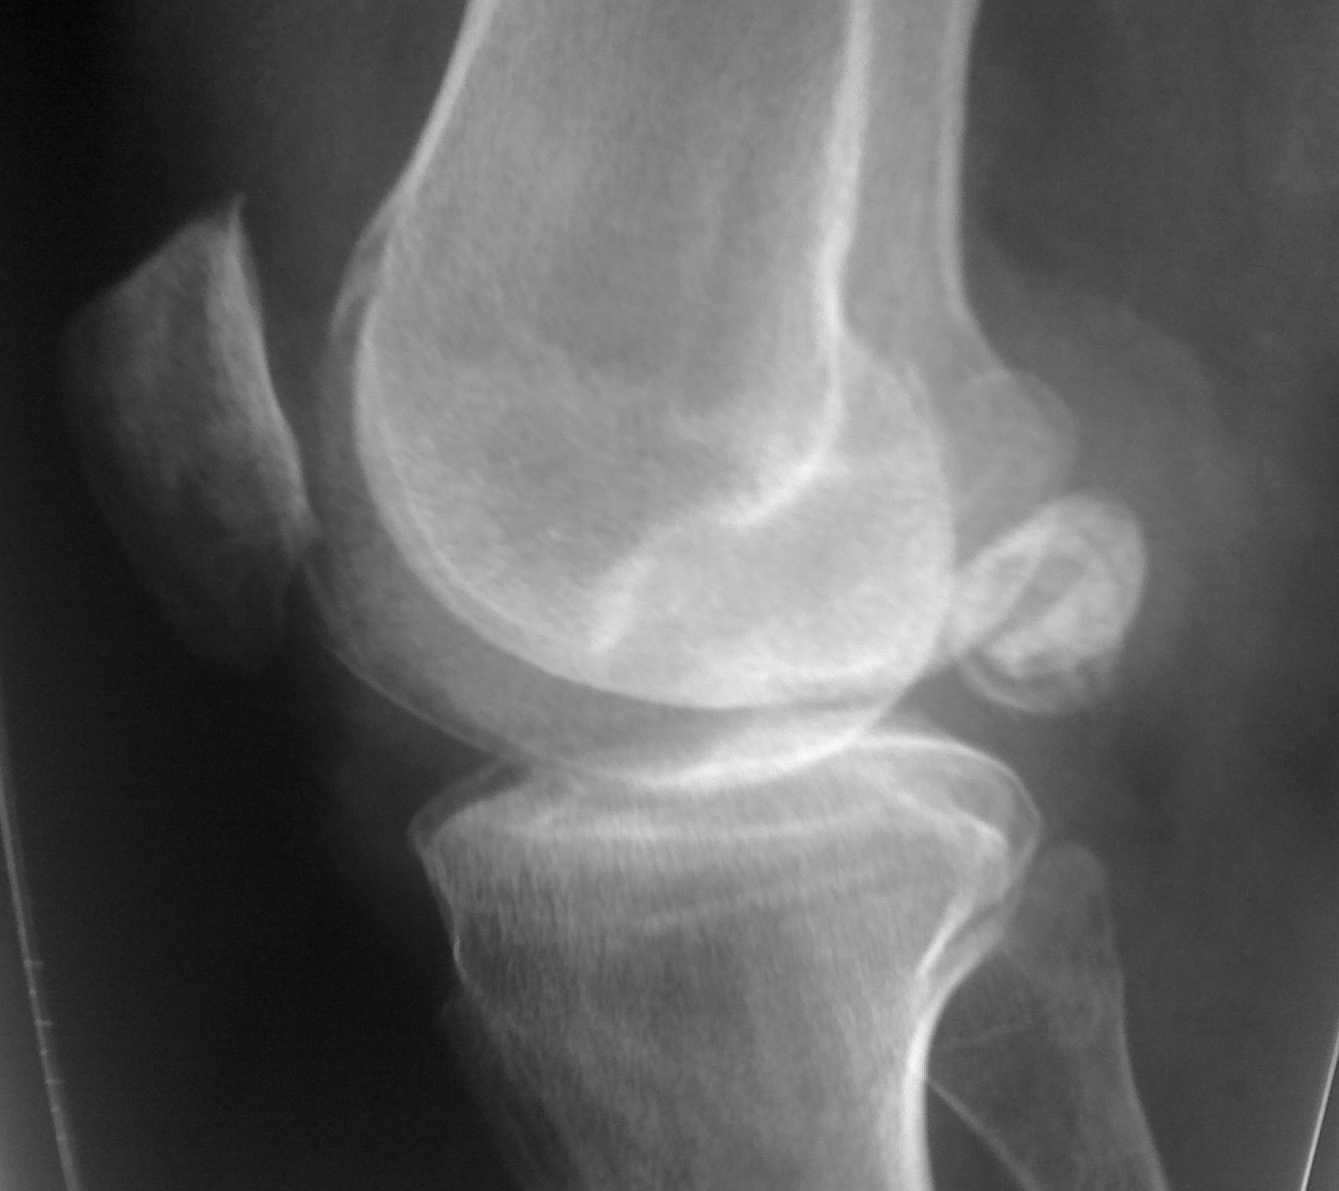

Нужен совет, а точнее ответ на вопрос нужна повторная операция или нет? Пациент 37 лет? активный образ жизни мотоцикл, лыжи и остальной набор развлечений. В марте 2010 оперирован-артроскопия левого коленного сустава, субтотальная резекция менисков? удаление 3-х свободно лежащих хондромных тела6 тунелизация мыщелков бедренной кости. Артроскопическая картина гонартроза 3 ст. С марта по июнь 9 раз пунктировался сустав эвакуировалась по 80-100 мл. светло-желтой синовиальной жидкости без хлопьев и примесей. Посевы отр. Анализы на инфекцию (хламидии и т.д.) дважды отр. Ревматолог-не их патология. В общих анализах без отклонений. В приложенном рентгене-тела в задних отделах как до так и после операции. Во время операции-прицельно их искали, но они вне полости сустава, что подтверждает МРТ. На контрольных ренгенограммах -смещение тел ни на миллиметр. Зеркальное отображение предыдущих. Болевого синдрома нет. Единственная жалоба пациента на наличие выпота в суставе. Температурной реакции нет. Сустав визуально не изменен. не "горяч". Тела в задних отделах не пальпируються. Дважды параартикулярно вводил дипроспан с интервалом в 4 недели. НВПС. Иммобилизация тутором, ударная "шокирующая" доза антибиотика-все по нулям. Дайте совет не ужели синовит поддерживаеться хондромными телами или что то другое. Пациент на повторную операцию 50 на 50. Спасибо! Всех с наступающим профессиональным праздником!!!

Что бы точно судить, фабелла это или нет, сделайте здоровое колено, для фабеллы слишком большой размер. Отдайте пациента профессионалам по артроскопии, которые спокойно, но не без труда уберут в/с тело из заднего отдела коленного сустава через задне-медиальные и задне-латеральные доступы. Через стандартные доступы его не увидеть, а оно вполне можеть раздражать колено и давать синовит. При рецидивах делать с тотальную синовэктомию артроскопически. Успехов.

В задних отделах похоже на внутрисуставное тело,правильно отмечено,что для "боба"-фабеллы оно крупное.Тогда надо удалять из небольшого поперечного разреза,как раньше некоторые авторы рекомендовали доступ для заднего рога мениска.Артроскопически я не представляю как,разве из какого-то нестандартного доступа?

А прямая проекция есть? Судя по боковой проекции картина гонартроза 3 сомнительна.

На мой взгляд перед принятием решения пациета необходимо дообследовать. Пациенту показана биопсия синовиальной оболочки и если есть в полости сустава какие либо включения то и их тоже . Мочевую кислоту брали ревматологи? В данной ситуации нельзя исключить вилезно-нодулярный синовиит или синовиит на фоне подагры. Согласитесь лечение этих заболеваний немного рознится.